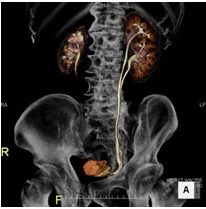

DWIBS法を使用した全身拡散強調MRIは、特に前立腺がんに多い骨転移に対して大変有効です。 そのため、前立腺生検により前立腺がんが確定した後の治療方針を決めるため転移の有無を確認するなどの目的にて行います。 また、前立腺がん治療後の再発や治療効果を評価するためにも撮影します。 前立腺癌以外にも、泌尿器がんの転移検索にも有効な検査です。